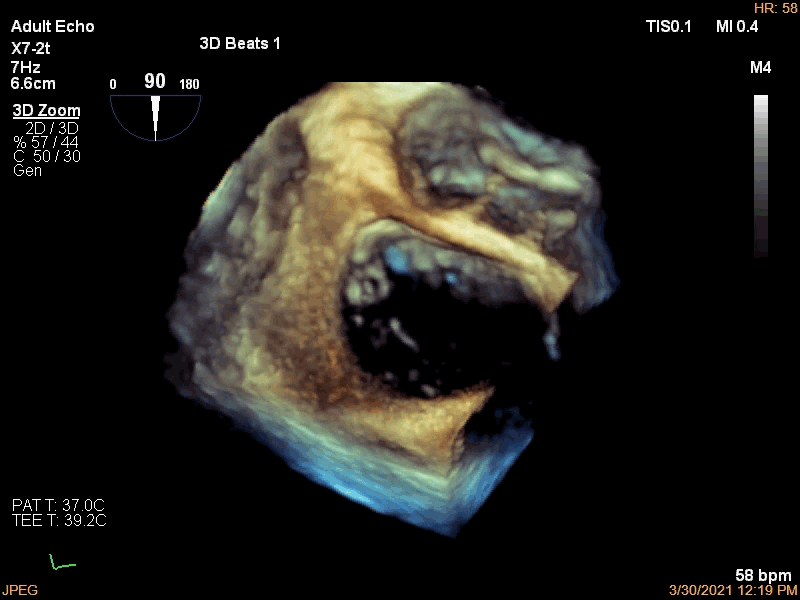

3月30日患者先在全麻下进行TEE(经食道超声心动图)再次评估瓣膜情况(视频4、视频5、视频6 ),确定为二尖瓣前组乳头肌断裂致二尖瓣前瓣脱垂并重度返流,其脱垂部位、瓣叶结构、瓣口面积等适合进行二尖瓣夹合术。术中IABP辅助,ECMO湿备,穿刺右侧股静脉,在TEE指导下顺利穿刺房间隔,随后送入二尖瓣夹合系统,在超声指导下于二尖瓣A2/P2区植入一枚Mitraclip XTR夹合器(视频7),术后TEE评估返流程度从5+降至1+(视频8 ),夹合结果满意,二尖瓣呈双孔启闭(视频9 ),术后二尖瓣平均跨瓣压差1mmHg(图1),收缩期肺静脉返流消失(图2 ),手术总耗时80min。香港亚洲医疗中心林逸贤教授通过视频连线进行手术全程技术支持。

视频4

视频5

视频6